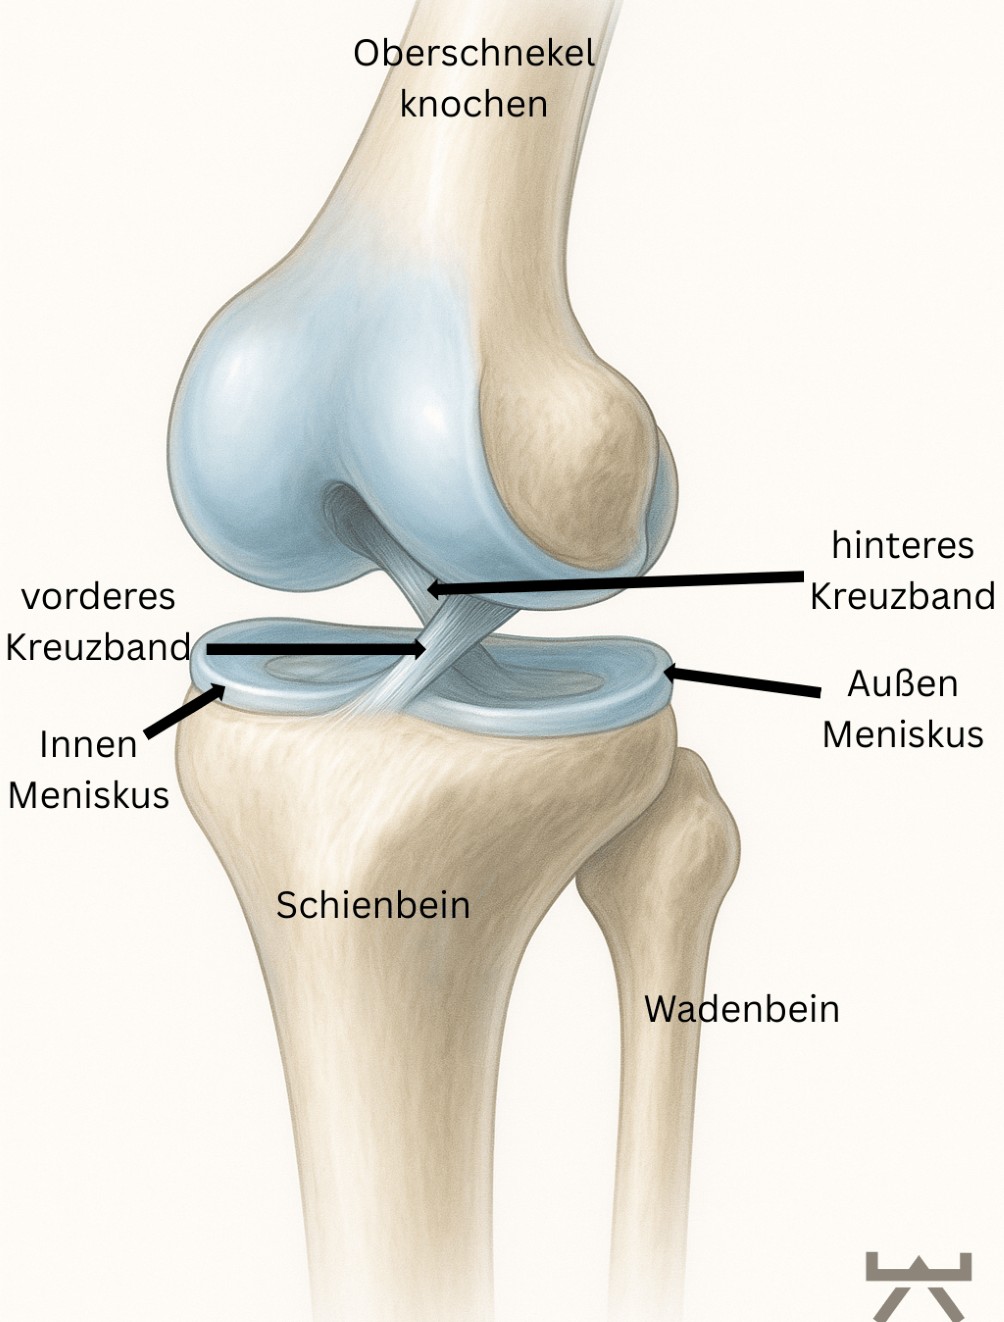

ANATOMIE

Das vordere Kreuzband (VKB) befindet sich innerhalb des Kniegelenkes und verbindet, als Bandstruktur zusammen mit dem hinteren Kreuzband, den Oberschenkel mit dem Unterschenkel.

Das vordere Kreuzband hat seinen Ursprung in einer kleinen Kuhle am Oberschenkelknochen und verläuft schräg zum Unterschenkelplateau, wo es mittig ansetzt. Das hintere Kreuzband verläuft genau gegensinnig und ist somit namengebend für die Kreuzbänder, welche sich durch ihre Verlaufsrichtung in der Mitte „kreuzen“. Jedoch müssen wir hier ergänzen, dass durch die individuelle Anatomie eines Menschen diese Ansatzpunkte variieren können, dies stellt bei einer späteren OP eines der größten Hindernisse in der Implantat Platzierung dar.

Die Aufgaben der Kreuzbänder sind vielseitig. Sie sind zum einen an der Stabilität des Kniegelenkes beteiligt. Nämlich beschränkt das VKB den Vorwärtsschub des Unterschenkels gegenüber dem Oberschenkel. Und das hintere Kreuzband (HKB) beschränkt den Rückwärtsschub des Unterschenkels gegenüber dem Oberschenkel. Jedoch sollte dies nicht die Hauptfunktion des Bandes sein, sondern ist die Stabilität des Kniegelenks vornehmlich die Aufgabe der gelenkumgebenden Muskulatur, sprich Oberschenkelvorder- und -rückseiten Muskulatur sowie der Wadenmuskulatur.

Deshalb ist eine gut ausgeprägte und koordiniert arbeitende Muskulatur einer der wichtigsten Schützer und somit Schlüsselpunkt in der Rehabilitation nach einer Verletzung, aber dazu später mehr.

Die zweite, essentielle Rolle des VKB, ist die dauerhafte Rückmeldung der auf das Knie einwirkenden Kräfte und Tiefensensibilität während der gesamten Bewegung. Dies kommt zustande da die gelenkumgebenden Band- und Kapselstrukturen eine Vielzahl an Mechanorezeptoren besitzen. Auch dieses System wird nach einer Verletzung bzw. einer OP deutlich beeinflusst. Darum gilt es auch hier einen Trainingsfokus gleich zu Beginn der Reha zu legen. 54,55